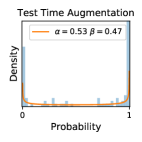

To model how different classifiers will respond to a given input , we assume that the prediction from classifier is sampled from a beta distribution that is characterized by two parameters by and . We further assume that is fixed to the same constant value for all ’s. Under this assumption, each input can be described by ( can be calculated since is fixed), easing further analysis. The Severity Level (SL) of the case represented by image can be characterized by the parameter . The larger the value of , the more severe the case of is. When and are close, the case is ambiguous as the distribution shifts towards being symmetric (i.e. signifying much disagreement among classifiers) rather than being one-sided (i.e. consensus among classifiers that is negative or positive). We provide a set of examples in Figure 2 and also Figure S.8 in the supplementary materials showing how the beta distribution can be used to capture diverse predictions given by an ensemble learner.

We conducted a case study on diagnosing diabetic retinopathy with ensembles of DL models. For benchmarking the performance of our ensemble-based solutions under the scheme described in Sec.3.3, we used two popular collections of diabetic retinopathy image data, the Kaggle Diabetic Retinopathy dataset [22] (hereafter referred to as “Kaggle-DR”) and the Messidor-2 dataset [23], each respectively consisting of and high resolution images. Diabetic retinopathy is graded into five SLs, as displayed in Figure 2. Following the problem setup used in previous papers [24], we trained models to distinguish the referable (SL2-4) cases from the non-referable ones (SL0 & SL1) (see Section B.1 for more detailed descriptions). We also tested our trained ensemble models on two o.o.d. image datasets (ImageNet [25] and CIFAR-10 [26]) to examine their capabilities of identifying o.o.d. inputs (see Section B in the supplementary materials).

In contrast, the MC-dropout method showed the worst overall performance among the three, as it can be seen from the high ratios of SL0 examples among the uncertain negatives in Figure 4. The histograms in Figure 2 provides another perspective to look into the phenomenon, where a decent proportion of MC-dropout model’s predictions on SL0 inputs entailed low confidence (far from 0 or 1), which from another angle explained why MC-dropout was less specific in terms of lower FNP; many no-DR inputs (i.e. SL0) were erroneously assigned high uncertainty by MC-dropout models.

It is still an open question why the evaluated MC-dropout networks signaled relatively high uncertainty on SL0 & SL3 & SL4 data that are less likely to be ambiguous. We conjecture that much of the “uncertainty” indicated by disagreement among test-time dropout samples actually reflects the stochastic nature of dropout networks rather than the real decision uncertainty associated with the data. It is worth noting that the MC-dropout model we evaluated was not weak per se; they all achieved above Area Under Curve (AUC) scores on test sets. The weakness of individual test-time samples (which explains their low-confidence predictions on SL0 & SL3 & SL4) might have been hidden when they are aggregated into an ensemble—a well-known advantage of ensemble learning. Our results suggested that the uncertainty information given by implicit ensemble methods such as MC-dropout and TTA might not be as reliable as that from explicit ensemble approaches (e.g., stacking ensembles). Similar findings on MC-dropout can be found in some previous papers [1].